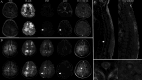

Results: Of the 30 patients with IVLBCL, 10 had neurological involvement and 20 without neurological symptoms, including myelopathy (5 patients, 50%); cognitive impairment (3 patients, 30%); seizures (2 patients, 20%); optic neuropathy, hemiparesis, homonymous hemianopia, vertigo and global aphasia (each affecting 1 patient, 10%). 60% of IVLBCL with neurological involvement had systemic symptoms, including prolonged fever, anaemia, anorexia and weight loss. MRI showed hyperintense lesions in the supratentorial, infratentorial and spinal cord with the prominent findings being longitudinally extensive cord lesions (four patients, 40.0%). The median survival time of the IVLBCL with neurological involvement was 4.1 months (95% CI: 0.0 to 17.1 months), with a 1-year survival rate of 37.5% and a 2-year survival rate of 25.0%.